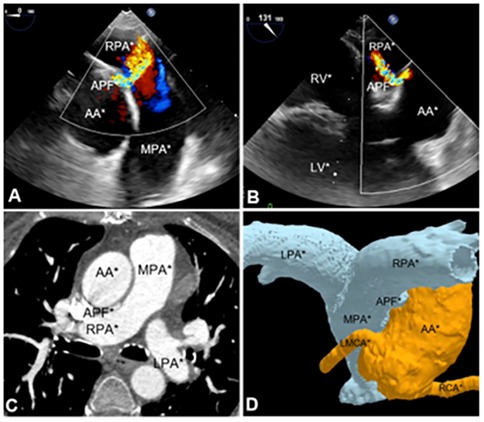

During the 9-month follow-up period, the patient demonstrated significant clinical improvement with resolution of symptoms. A follow-up CTA of the aortic and pulmonary vessels confirmed the correct position of the device (Figures 3A–D), with a slight protrusion into the lumen of the proximal right pulmonary artery. TEE showed no evidence of pulmonary artery flow obstruction, pressure gradients, or hemodynamic compromise.

Figure 3

Images of aortic and pulmonary vessels angiotomography (A,B) performed after aortopulmonary fistula correction procedure, during the follow-up and its 3D reconstruction (C,D).